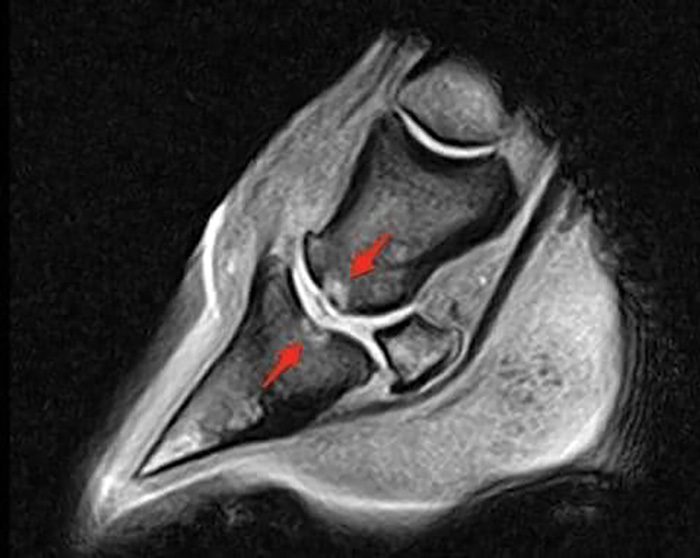

This MRI is an example of a bone bruise on the coffin bone and short pastern that occurred because of rapid deceleration on synthetic footing.